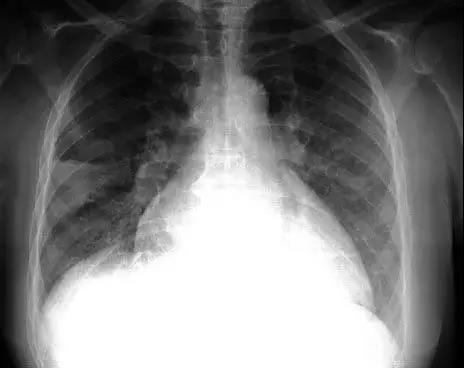

在晚期非小细胞肺癌的治疗过程中,癌细胞产生治疗抵抗是到目前为止都无法解决的临床难题,越来越多的证据表明癌症干细胞是具有形成肿瘤并进行无限制自我更新能力的一群特殊细胞,传统治疗方法常常无法完全杀灭癌症干细胞,这也是导致治疗后复发和转移的关键原因。